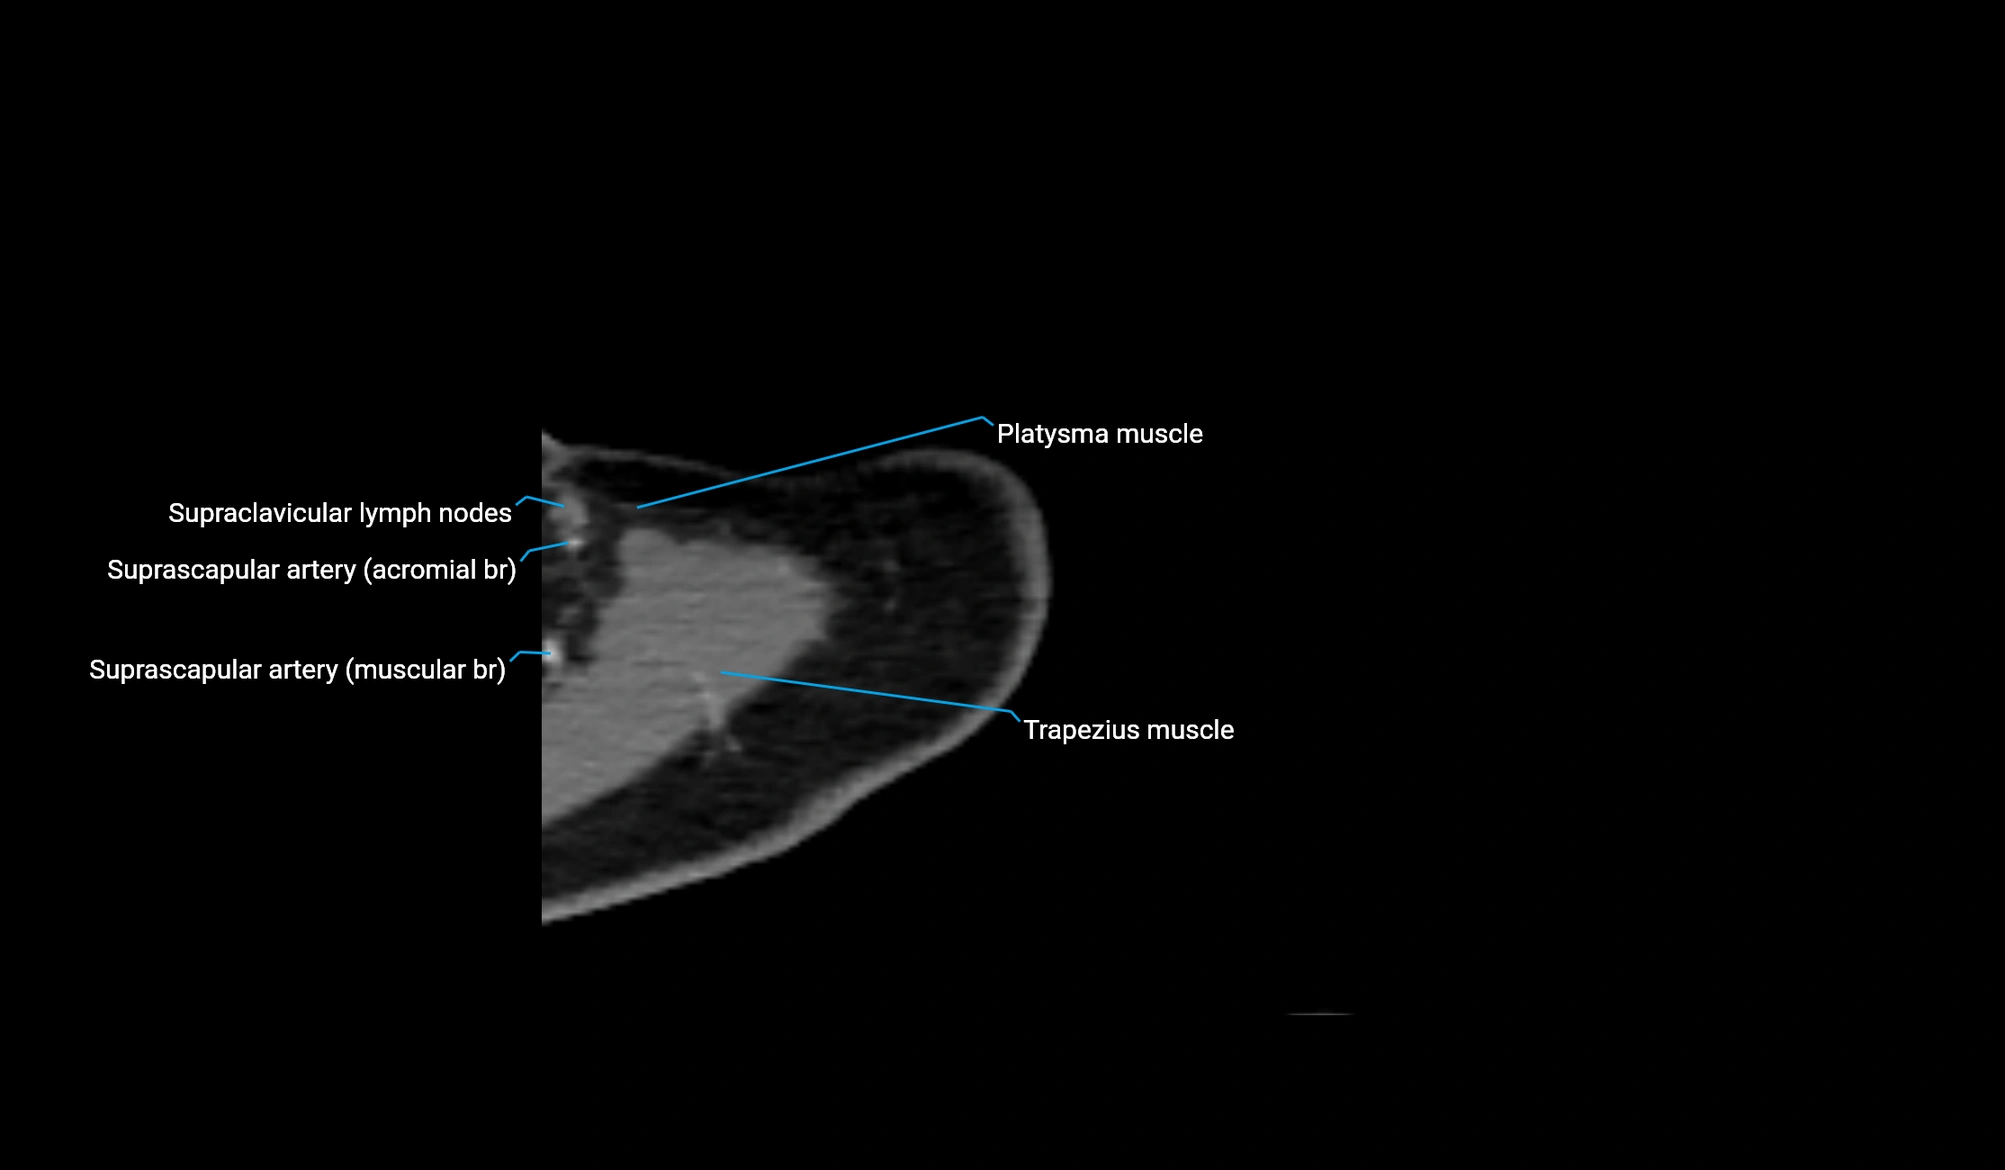

MRI image